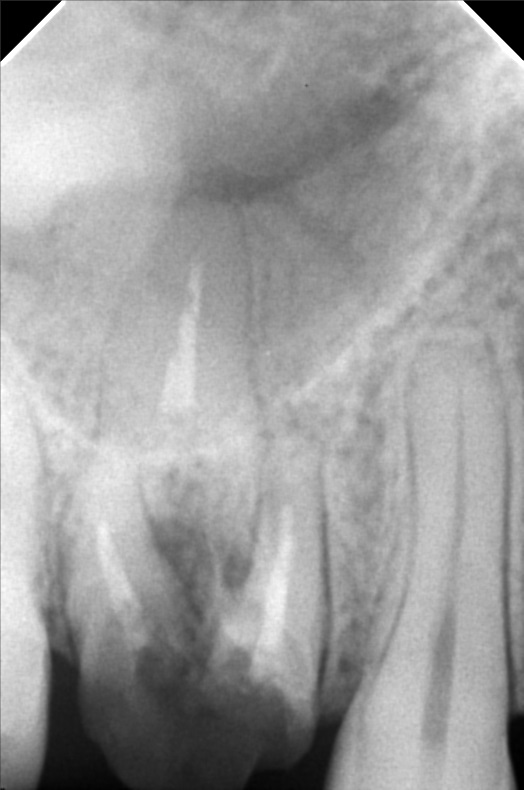

Edit Record Check our patient data records. Add patient information Patient Info Profile picture Last Name First Name Middle Name Birthdate Age Street Barangay City Country Zip Code Contact number Email Procedure 01/16/20 #18 niti lower #41 RW (distal) 09/17/21- exo 16/ upper for removal lower teeth- 34^ 16*16ssL 4/21/22- Implant #16 4.3 x 10mm with sinus lift #36 4x3 x 10mm under Iv CS 09/06/22 peri implantitis/ currettage and debridement/ ozone/ CGC/PRF/ bone filler- bio oss 025g 10/5/22 - CHECK UP; PRESCRIBED VIT D 1000IU; 0.9%NSS; ORAHEX 11/04/22-2healing Ab. 12/13/22- Pick up impression 12/24/22- IntsofCrown 5/06/23- Odontectomy tooth #12/Compound odontoma removal GBR-double oss cancellous and cortical bone 1cc and .25 cc with xenograft .25g/PRF-GTR Trapezoidal flap under IV conscious sedation non resorbable suture-nylon Specimen histopathology 05/20/23- removal of suture/ozone therapy/LC 46 mesial, Occlusal, buccal removal of amalgan 46 06/29/23- check up/xray/rem bal 3200 08/25/23-#12 Build Up/ Lingual retainer/OP 3200 BALANCE USED 04/19/24 check up LC #36 Occlusal of crown #26 lingual pit 05/25/24 3D scanning 10/04/24 #12 4mmx 11.5mm w/ incidental graft 1CGF 3 PRF membrane Odontectomy #38 10/12/24 attachment of temporary teeth 03/14/25 install healing abutment OP 05/01/25 3D scanning #12 full contour top abutment O/D: 5 G/H: 3MM A/H: 8MM 01/31/26 LC#37-B OP w/polish File micheal_2.jpg File 2 micheal.jpg File 3 img_20220421_171028.jpg File 4 300391815_794848065019598_3764074978376967115_n.jpg File 5 301522684_1451524321981960_1833940363743363873_n.jpg File 6 borja-m.jpg File 7 img_20221227_110757.jpg File 8 img_20221227_110831.jpg File 9 1000000484.jpg File 10 img_20241004_153433_742.jpg File 11 File 12 File 13 File 14 File 15 File 16 File 17 File 18 File 19 File 20 Retain Record Retain Record Yes No Save Your Changes